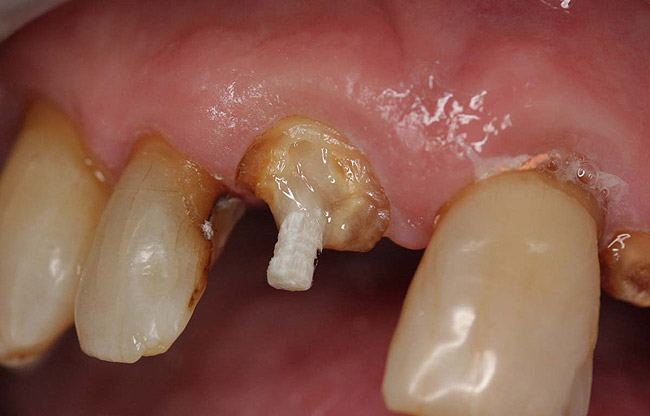

Case 1

A Class IN maxillary bicuspid was previously restored with a fiber post and an all-porcelain crown (Figure 1). The forces of the oral environment resulted in fracture of the fiber post and crown failure. The remaining fiber post in the root was removed, and anti-rotational areas were prepared for a cast post (Figure 2). A gold cast post was constructed at a dental laboratory, using an indirect technique (Figure 3). A porcelain-fused-to-metal (PFM) crown was constructed with a bevel finish to provide a ferrule and reduce forces on the post (Figure 4 and Figure 5).

Figure 2  Same second bicuspid as Figure 1 after removal of the fractured fiber post.

Figure 2